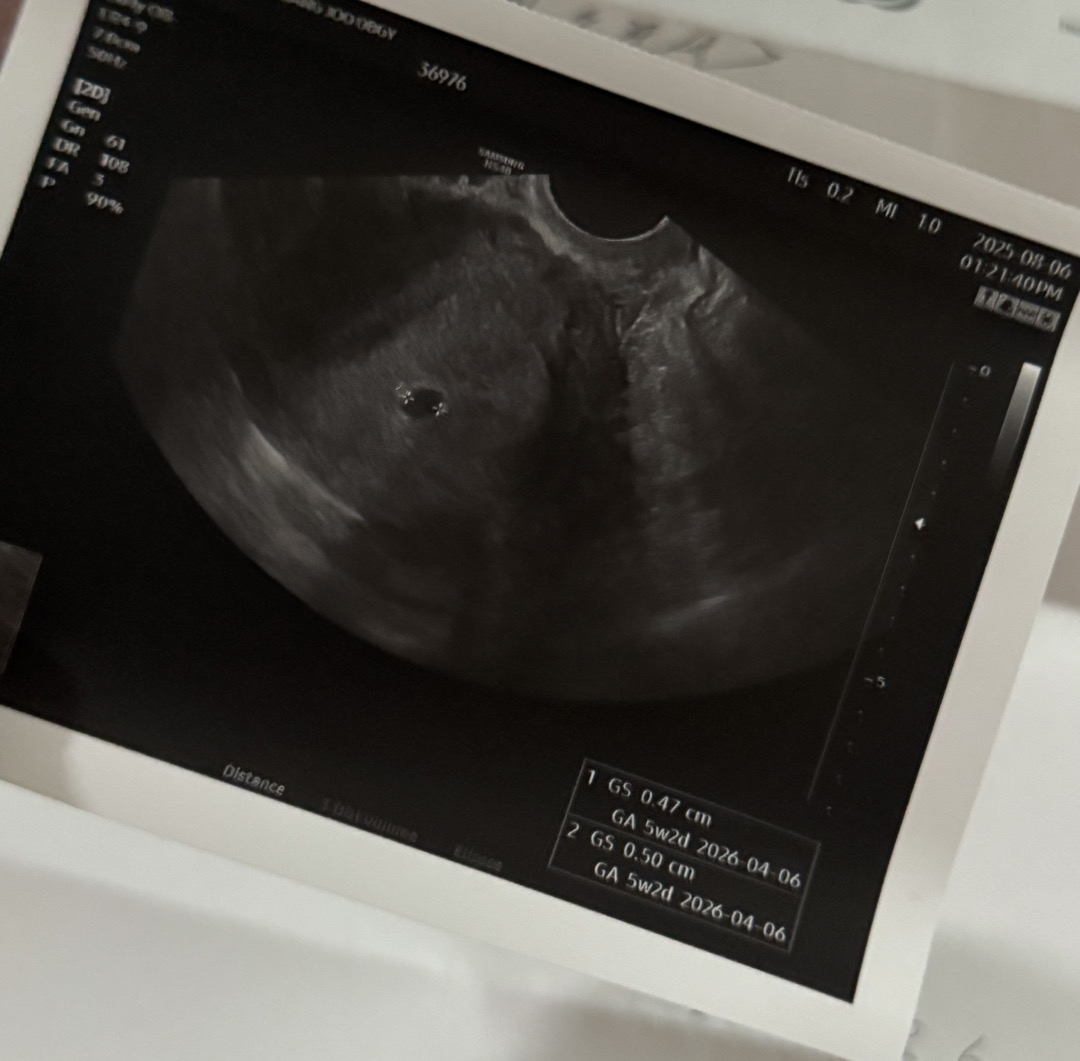

초음파 보고왔어요!

원래 생리가 불규칙적이라 매달 해보는데 항상 1줄이어서 오늘도 가벼운 마음으로 했는데 두줄이 너무 선명한거있져?ㅠㅠ 바로 남편 점심시간에 같이 병원 빠르게 다녀왔는데 아기집까지 보고왔어요🫶